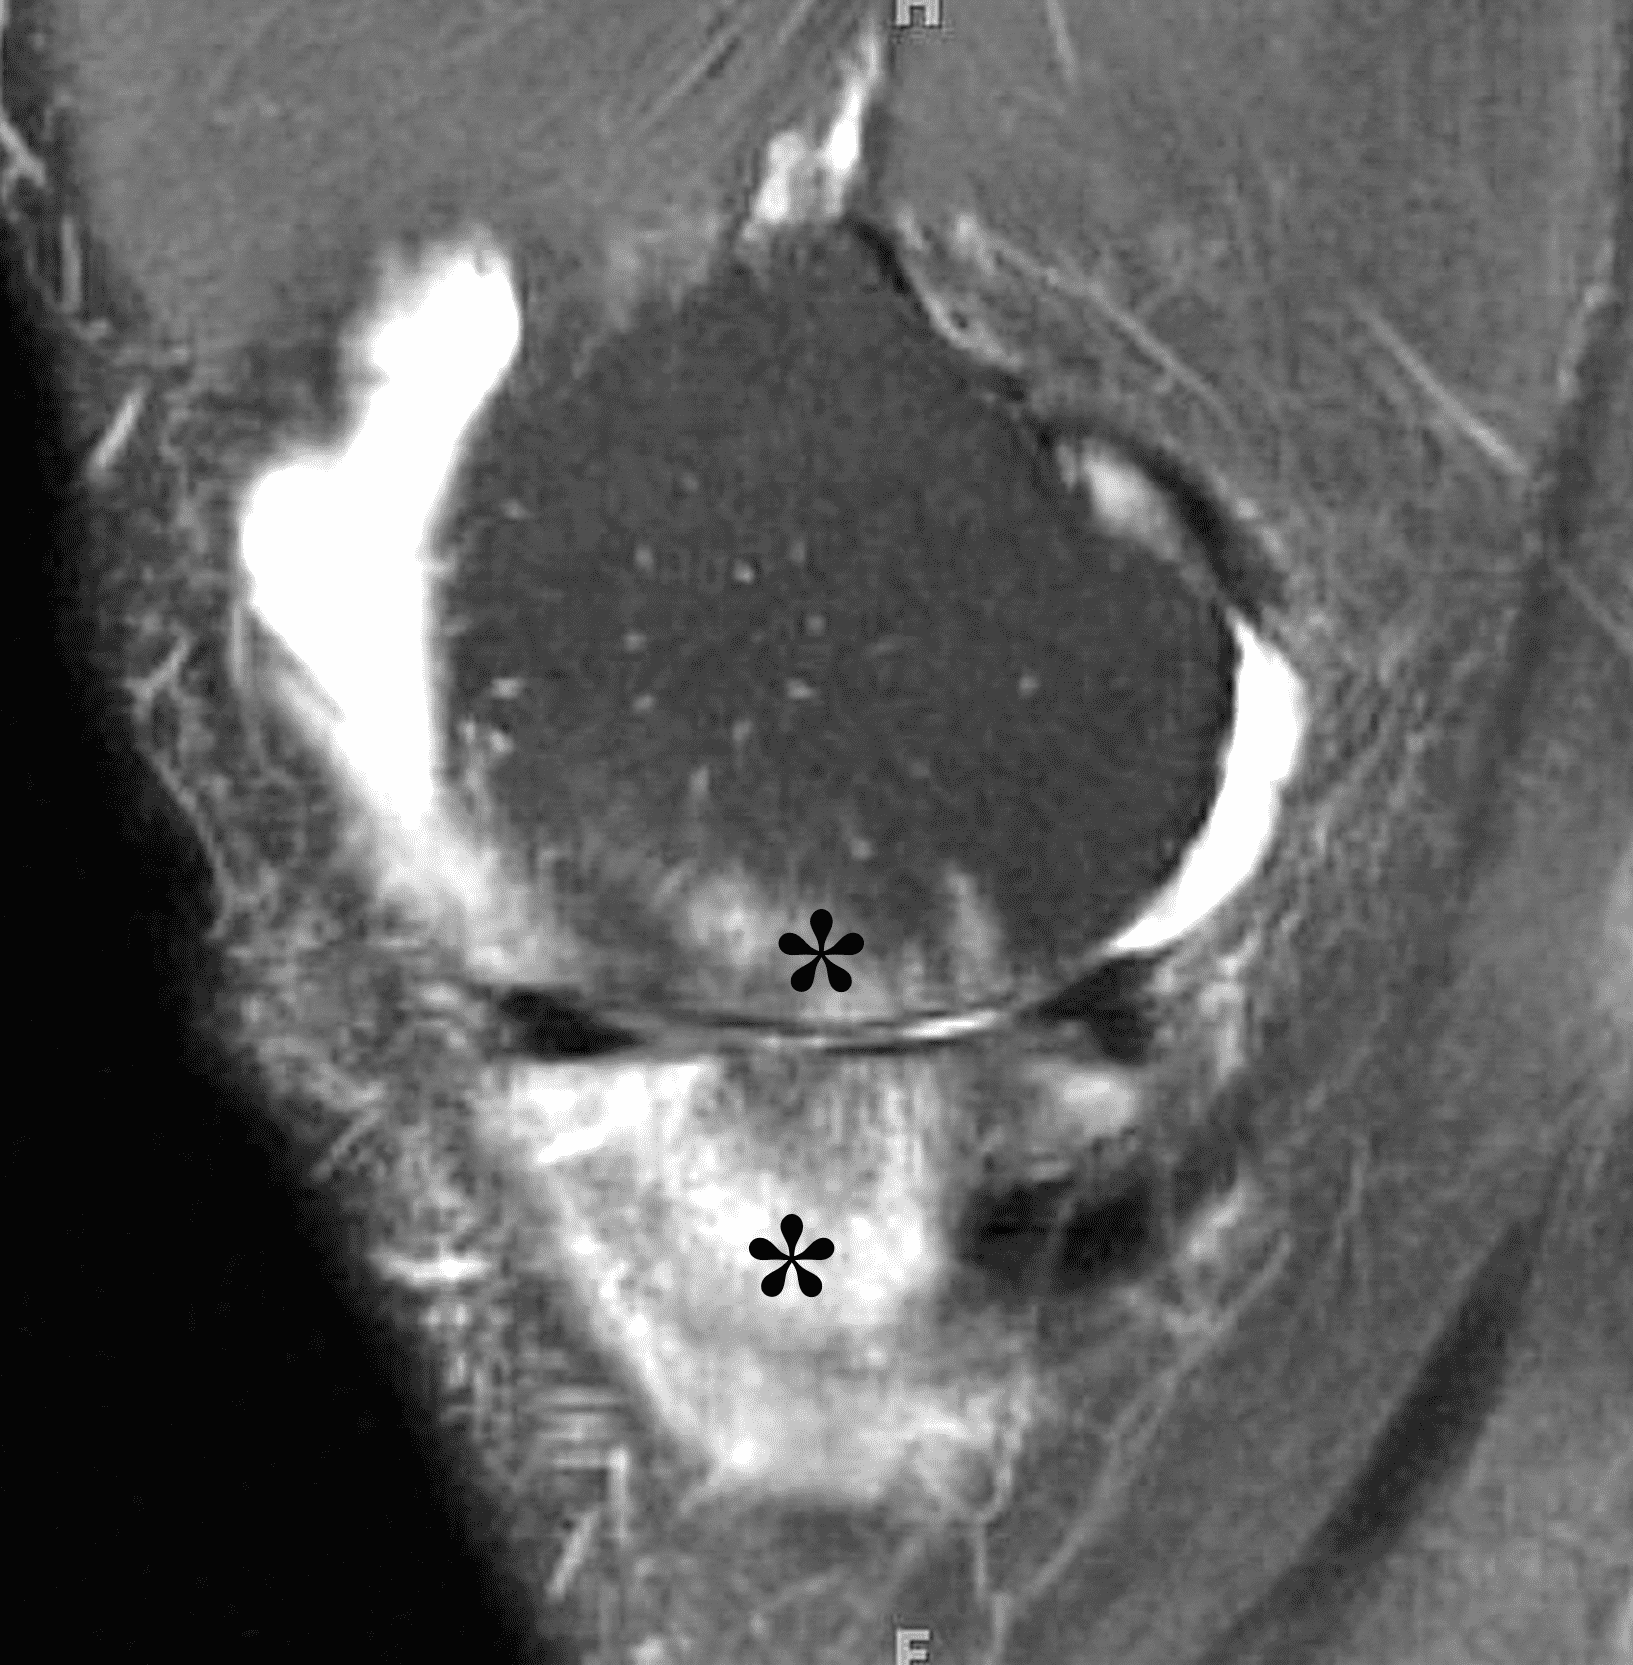

Figure 2: (2A) The coronal image shows a large effusion and severe hypertrophic synovitis (asterisks) in the knee. (2B) On the sagittal image the hypertrophic synovium (asterisks) involves the suprapatellar and infrapatellar recesses as well as the anterior and posterior intercondylar notch. A reactive lymph node (arrow) is present in the popliteal fossa. (2C) The axial image demonstrates myositis (arrows) involving the popliteus and peroneus longus muscles. Note the preserved articular cartilage, lack of erosions, and the absence of subcutaneous or marrow edema.

The causative spirochete invades the synovium, triggering a host inflammatory response that leads to synovial hypertrophy and inflammation, resulting in the characteristic clinical symptoms and imaging findings associated with Lyme arthritis.2 Common MR findings associated with Lyme arthritis include synovitis, joint effusion, popliteal lymphadenopathy, and myositis predominantly involving the popliteus (Figure 4).2,3,9 In contrast to acute septic arthritis due to more common bacteria, subcutaneous edema, marrow edema, erosions, and osteomyelitis are uncommon (Figure 4C).

Figure 4: Lyme arthritis. Fat-suppressed, fluid-sensitive images. (4A) Transverse image shows severe proliferative synovitis in the anterior and posterior joint recesses (arrows). Note the lack of surrounding subcutaneous edema. (4B) In addition to synovitis, the sagittal image shows multiple reactive lymph nodes (red arrows) and popliteal myositis (white arrow). (4C) Coronal image also shows patchy non-joint centered marrow edema in the distal femur and proximal tibia (asterisks), which is uncommon in Lyme disease compared to acute septic arthritis.